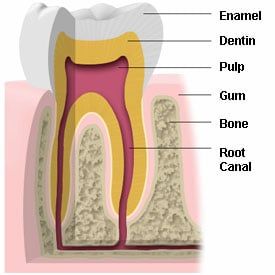

Baby bottle tooth decay or syndrome is a form of tooth decay that can destroy the teeth of an infant. This decay may even enter the underlying bone structure, which can hamper development of the permanent teeth. The teeth most likely to be damaged are the upper teeth.

Baby bottle decay is caused by frequent and long exposure of a child's teeth to liquids containing sugar such as milk, formula, fruit juices, pop and other sweetened liquids. These liquids fuel the bacteria in a child's mouth, which produces acids that attack enamel.

This is due to the risk of fluorosis in younger children that swallow toothpaste during regular brushing. A child may face the condition called enamel fluorosis if he or she gets too much fluoride during the years of tooth development. Too much fluoride can result in defects in tooth enamel.

How Enamel Fluorosis occurs

By swallowing too much fluoride for the child's size and weight during the years of tooth development, a child can develop enamel fluorosis. This can happen in several different ways.